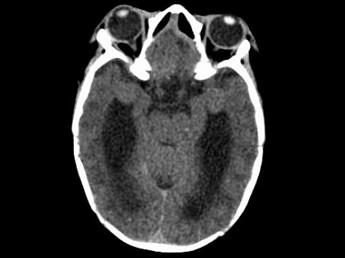

问题 两个月女婴,口咽部有一肿块,行CT检查如图,请选择最可能的诊断 ( )

选项 A、前脑无裂畸形 B、Dandy-Walker综合征 C、胼胝体发育不全 D、透明隔囊肿 E、脑积水

答案 C